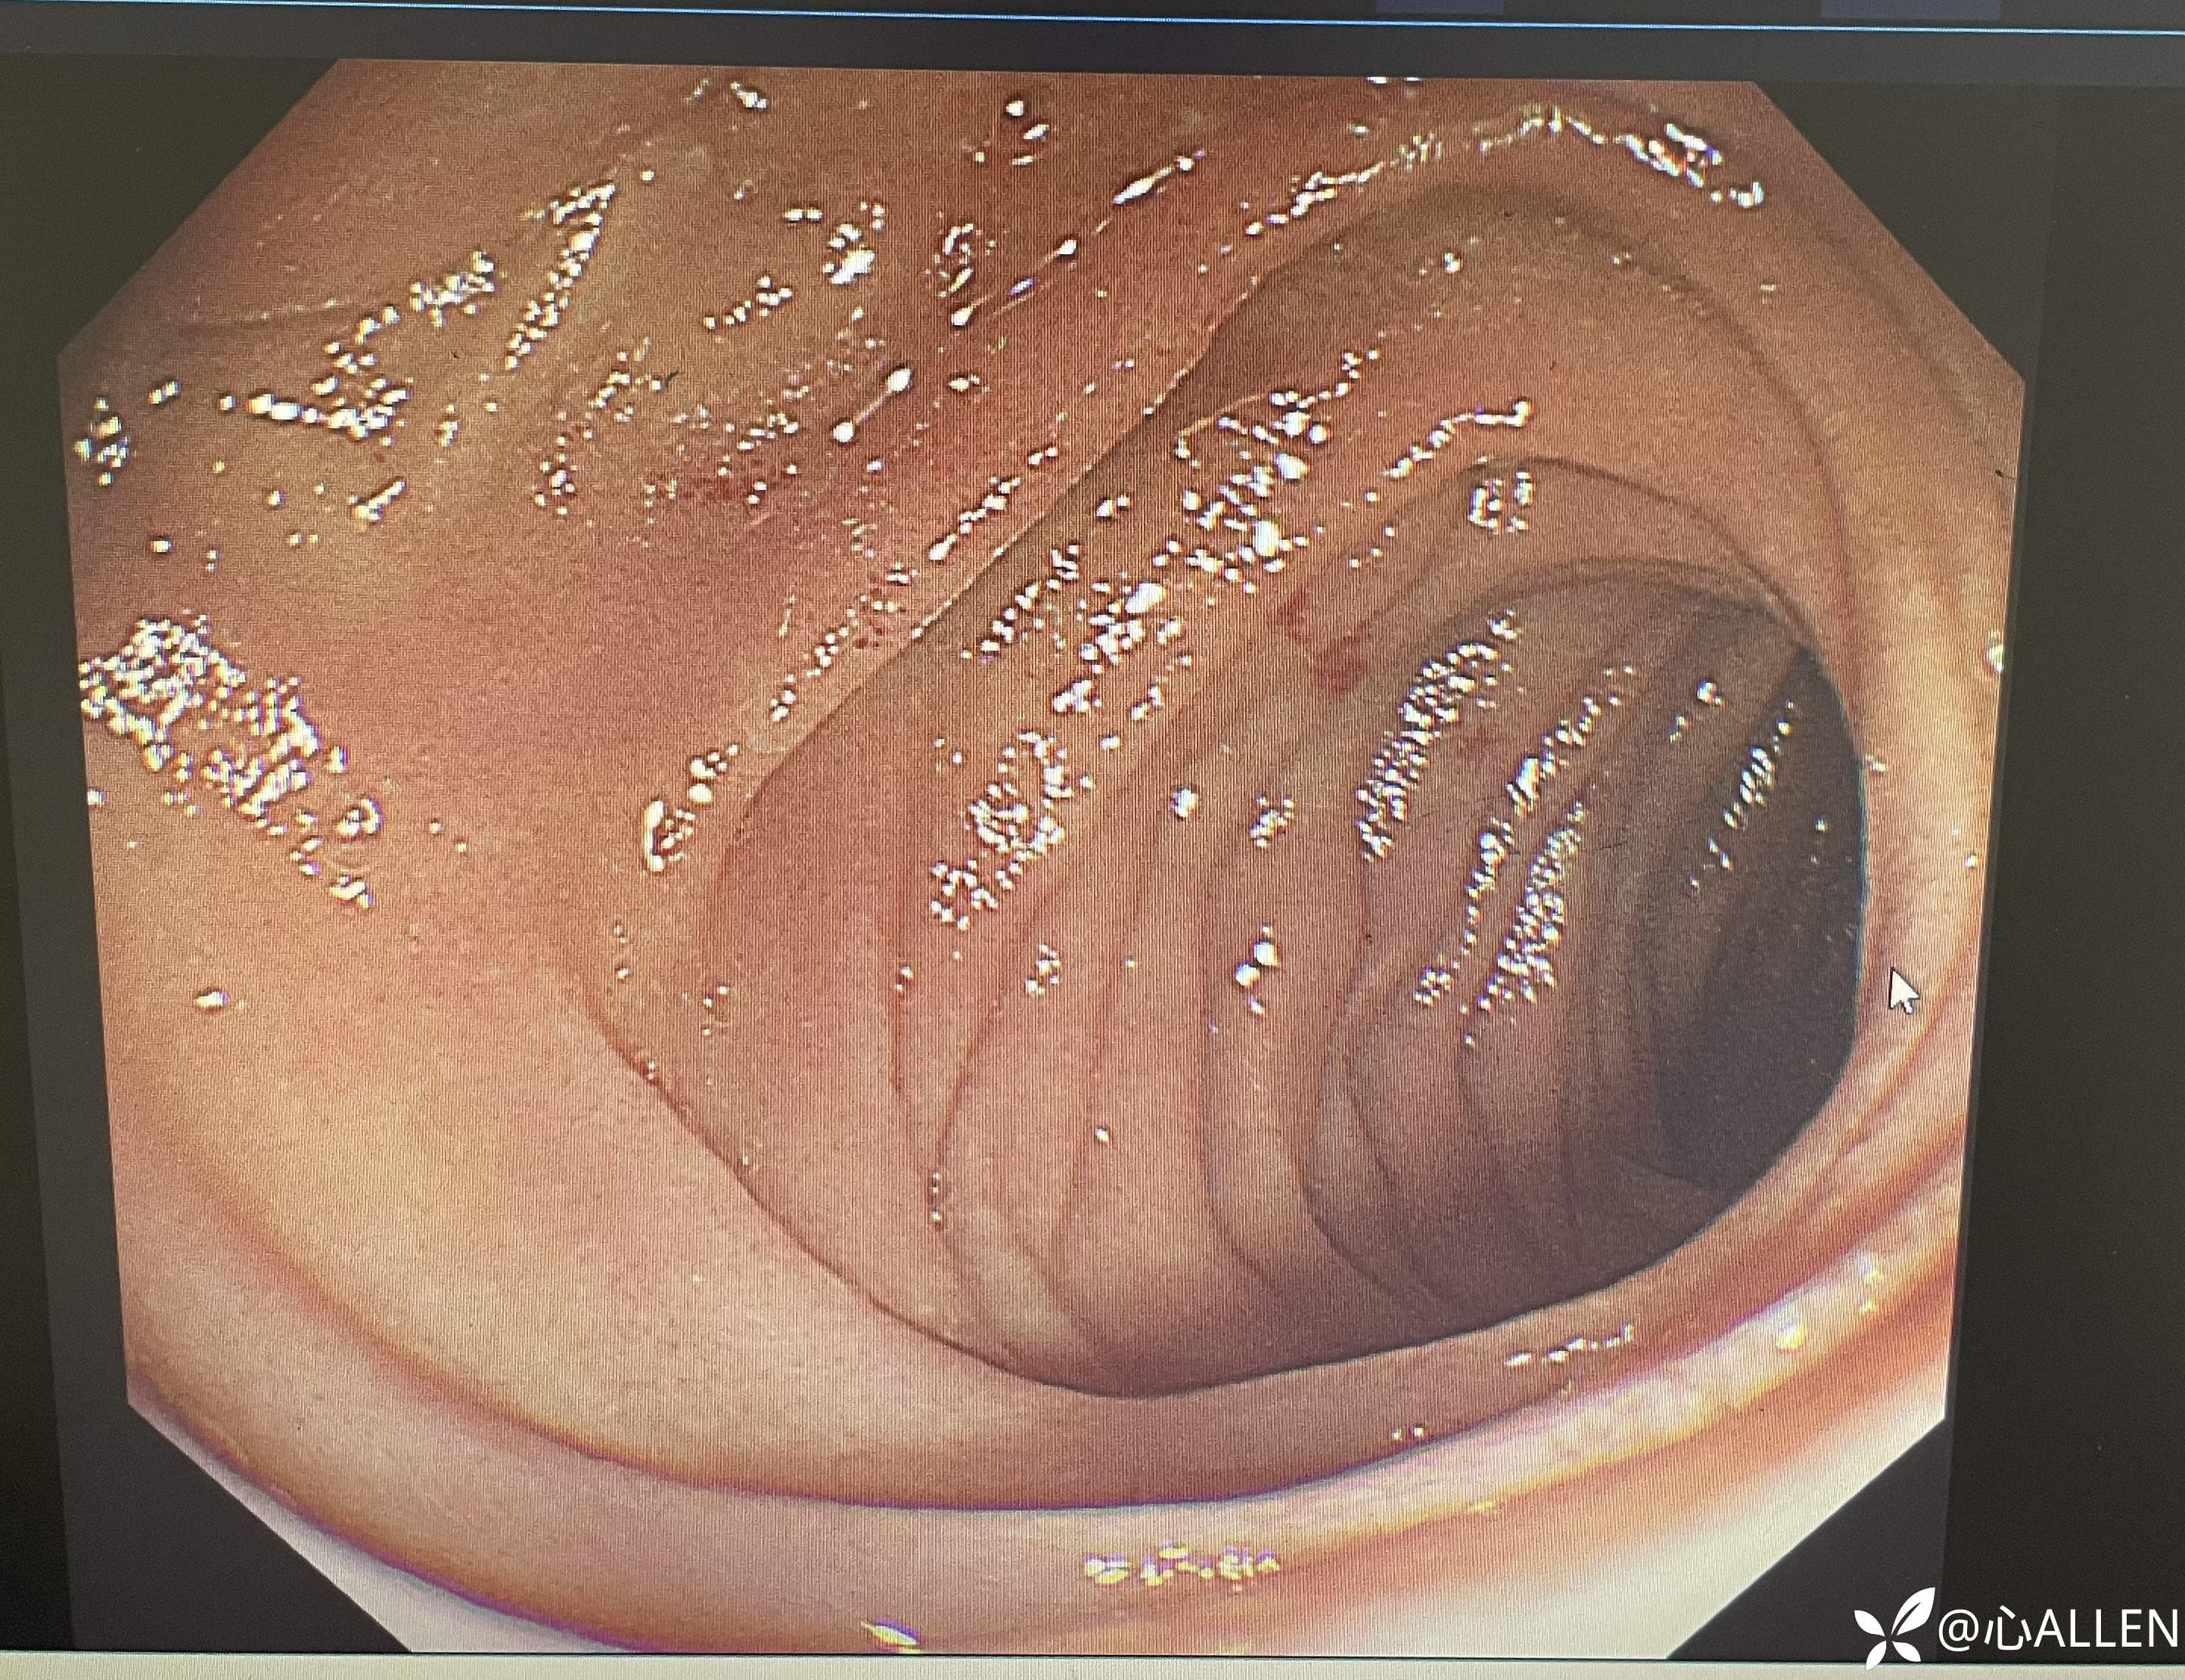

胃窦及幽门

进镜观察到扩大的球腔,远端似有主乳头